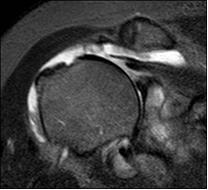

Per stabilire la presenza di una lesione di cuffia il primo passo è la visita dell’Ortopedico, che può sospettarla valutando con una serie di manovre i movimenti della spalla e la forza in varie direzioni. Questi test specifici sono mirati a valutare l’escursione articolare della spalla, la forza impressa dai differenti tendini all’articolazione della spalla e l’eventuale dolore causato nel corso delle manovre. In caso di lesione di un tendine generalmente si potrà apprezzare la riduzione della forza nel test che valuta quello specifico tendine, aspetto che non sempre è correlato alla comparsa di dolore durante la valutazione stessa. Gli esami strumentali principali sono l’Ecografia, che viene effettuato mediante una sonda a ultrasuoni, e la Risonanza Magnetica Nucleare. La prima è una metodica economica e diffusa, che può essere considerata l’esame di screening. La risonanza visualizza le strutture della spalla sfruttando i campi magnetici, è più costosa, è anche più difficile da tollerare per alcuni pazienti ed è controindicata in presenza di alcune condizioni. Le informazioni che fornisce sulla cuffia dei rotatori sono però molto più complete, soprattutto quando si deve valutare un intervento di riparazione (fig. 5).

Quando si osserva una lesione a tutto spessore della cuffia, oltre alle dimensioni e alla sede, è importante valutare altre due caratteristiche che la risonanza magnetica consente di studiare accuratamente: il grado di retrazione del tendine rotto, ovvero quanto si è allontanato dal suo punto di inserzione all’osso, e il grado di atrofia del muscolo a monte della rottura, che può andare incontro ad un processo di involuzione in cui le fibre muscolari vengono via via sostituite da tessuto grasso. Questi aspetti hanno ricadute sulle decisioni inerenti la scelta del trattamento.